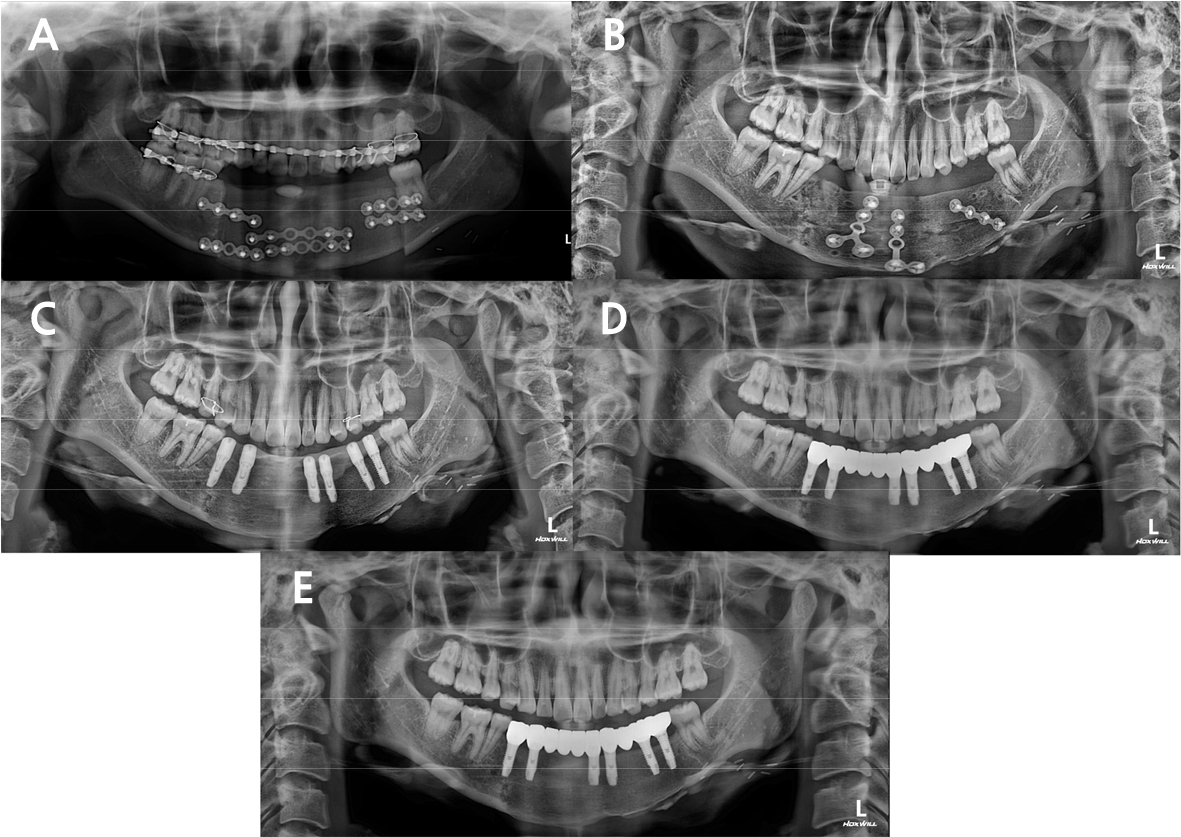

Fig. 3.

(A) Due to the recurred odontogenic keratocyst in the mandible, the patient underwent segmental mandibulectomy and iliac bone flap surgery, (B) 14 months later, additional iliac block bone graft was performed, (C) 7 months after the additional bone graft, delayed implant placement was performed, (D) 4 months after the implant placement, the temporary prosthesis was delivered. (E) 2 years after the implant placement, panoramic radiograph was taken. No significant MBL or symptoms were found.

Seven implants in three patients failed, all of which had bone exposure complications (Table 2). Fig. 3 shows a typical case of implant success. The 5- and 10-year implant survival rates were 95.0% and 91.5%, respectively (Fig. 4A). When only a bone graft was performed, the survival rate of implants was 96.9%; for DO with or without a bone graft, the survival rate was 87.5%; and with neither, the survival rate was 75% (Fig. 4B). When bone grafting was not performed or only DO was performed, the survival rate of implants was 60%. The survival rate of implants was 97.3% for iliac bone grafts. (Fig. 4C).